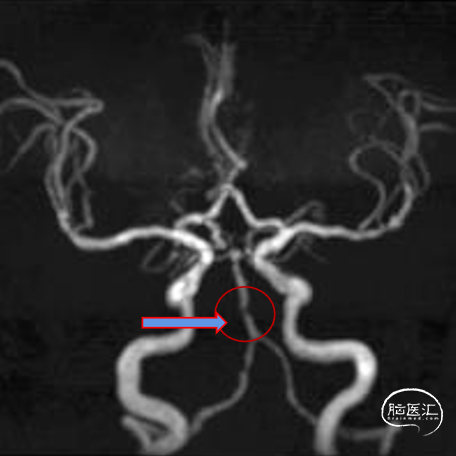

MRA:基底动脉重度狭窄

造影示:右侧优势椎,经右侧椎动脉导弯造影,双侧胚胎型大脑后动脉。

基底动脉狭窄位于双侧AICA开口处,且无双侧PICA,其供血区由双侧AICA、SCA分支代偿供血。

术前DSA:双侧后交通动脉开放。